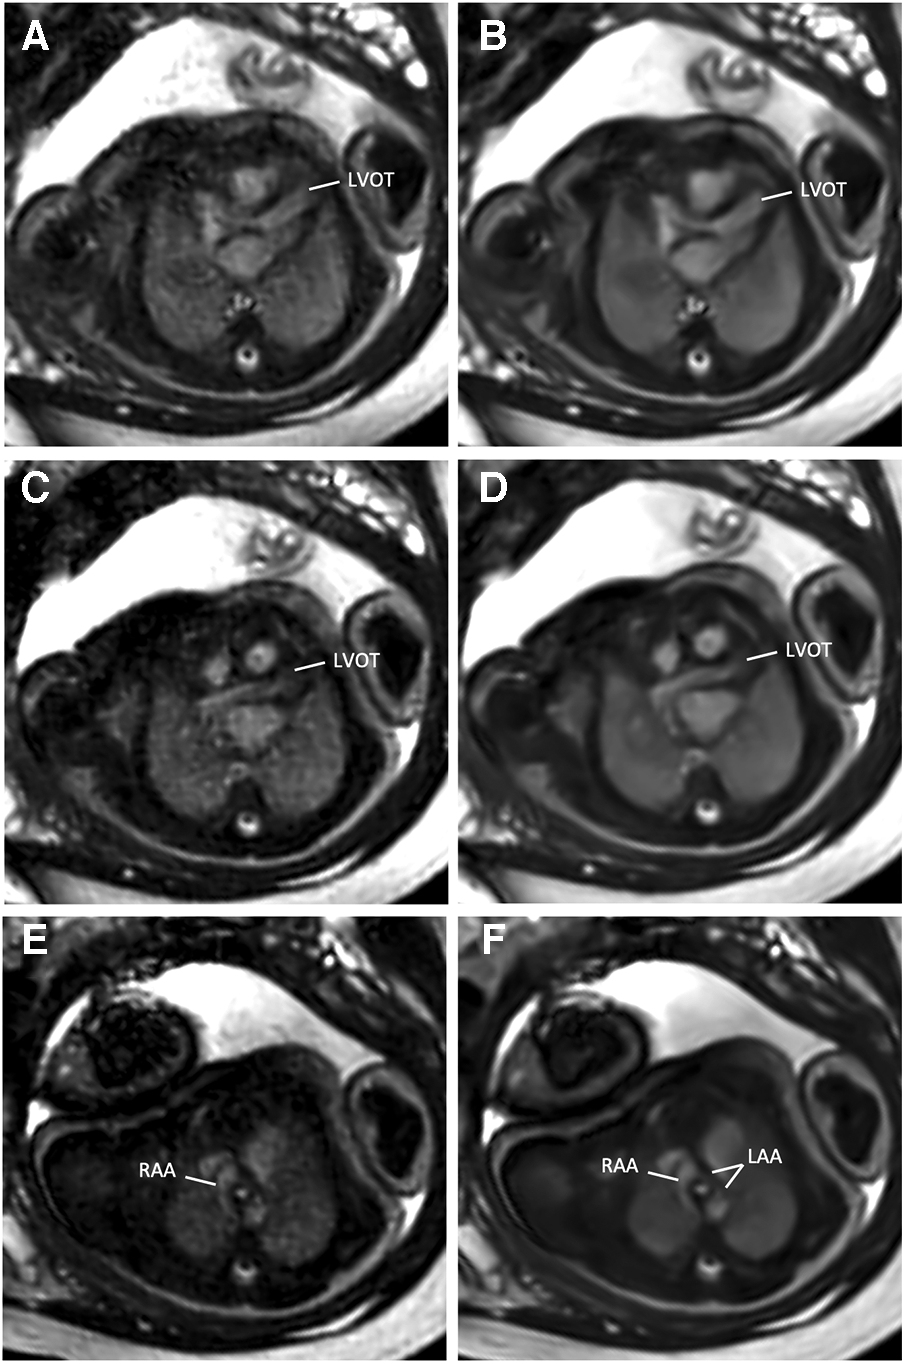

Confidence in diagnostic reading was rated higher when the bSSFP DL cine images were used to assess different cardiovascular structures (see Figure 4 and Table 4). Image examples demonstrating higher diagnostic confidence of bSSFP DL images for evaluation of the atrioventricular valves in a fetus with an intermediate-type atrioventricular septal defect and evaluation of the double aortic arch in another fetus are provided in Figures 5, 6.

Figure 5

(A,C,E) Standard CS and corresponding (B,D,F) DL image reconstructions of an axial balanced steady-state free precession cine sequence in a 38-year-old woman at a gestational age of 35 weeks and 2 days with a double aortic arch of the fetus. DL denoised images provided better delineation and diagnostic confidence of cardiovascular structures from the left ventricular outflow tract (LVOT, A–D) to the aortic arch level (E,F). While the dominant right-sided aortic arch (RAA) can be clearly delineated with both reconstruction models (E,F), the narrow left-sided aortic arch (LAA) is more clearly visible in the DL denoised image (F).

The DL model used in this study has been proven to alleviate the limitations of CS techniques in knee and prostate MRI and in MR cholangiopancreaticography and has received 510(k) clearance from the U.S. Food and Drug Administration (22, 23, 36, 37). Therefore, the purpose of this study was to evaluate the performance of the technique for feasible and easy-to-implement image denoising of fetal cardiac cine images in a clinical setting of fetuses with various forms of CHD. Quantitative analysis revealed a higher apparent signal-to-noise ratio and contrast-to-noise ratio of the DL cine reconstructions than the standard CS cine reconstructions (P = 0.002 and P < 0.001, respectively). In addition, qualitative reader assessment indicated that the DL cine reconstructions improved image quality, particularly in terms of endocardial edge definition and contrast (P < 0.001). These results are in concordance with previously reported measurements in prostatic lesions and intrahepatic bile ducts (23, 36). Furthermore, the level of diagnostic confidence was increased for six different cardiovascular structures, including the cardiac chambers, foramen ovale, valves, great thoracic vessels, aortic arch, and pulmonary veins. This could be of particular relevance for a precise analysis of ventricular morphology, size, and function to assess univentricular vs. biventricular outcomes in the borderline left ventricle (11). Another possible diagnostic benefit of better depiction of the foramen ovale might exist in hypoplastic left heart syndrome or dextro-transposition of the great arteries with unclear interatrial communication due to poor acoustic windows in late gestation, potentially leading to changes in delivery mode planning with catheterization laboratories on standby or not (11). Although the level of significance was weaker compared to the other structures (P = 0.031), the delineation of the aortic arch and the pulmonary veins could also be improved by using the DL cine reconstructions for diagnostic reading. This would be advantageous, for example, for better visualization of anomalous pulmonary venous connections or for the evaluation of aortic isthmus stenosis, which is considered one of the most underdiagnosed conditions in prenatal echocardiography (38). Although no aortic isthmus stenosis was present in this study sample to verify this, in one fetus with a double aortic arch, the smaller left-sided aortic arch could be more clearly delineated using the DL reconstructions compared to the standard CS reconstruction (Figure 5). However, to gain additional diagnostic information on extra-cardiac vessels alongside fetal echocardiography, it is worth noting that the inclusion of phase-contrast flow measurements and 3D volume datasets may be beneficial compared to 2D cine imaging alone.